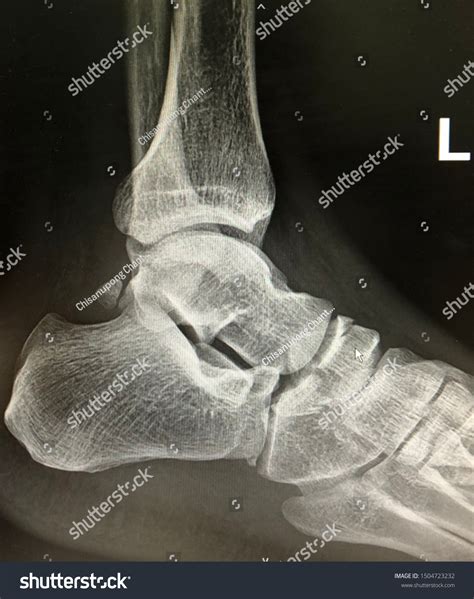

Lateral Ankle Xray

A Lateral Ankle Xray is a specific type of X-ray that provides a side view of the ankle. This view is particularly useful for assessing the alignment of the bones and identifying fractures or dislocations. The lateral view complements other views, such as the anteroposterior (AP) and mortise views, to give a comprehensive picture of the ankle's condition.

Interpreting a Lateral Ankle Xray requires a trained eye to identify key features and abnormalities. Some of the important aspects to look for include:

• Bone alignment: Ensuring that the bones are properly aligned and there are no signs of fractures or dislocations.

• Joint space: Assessing the width and uniformity of the joint space to detect any signs of arthritis or other joint issues.

• Soft tissue swelling: Identifying any swelling or inflammation around the ankle that may indicate an injury.

Radiologists and orthopedic specialists are trained to interpret these images and provide a detailed report of their findings. This report is then used to guide treatment decisions.

Some of the common findings on a Lateral Ankle Xray include:

• Fractures: Visible breaks in the bones, which may be simple or complex.

• Dislocations: Misalignment of the bones, often due to severe trauma.

• Osteoarthritis: Changes in the bone structure and joint space indicative of degenerative joint disease.

• Soft tissue swelling: Inflammation or edema around the ankle, which may be due to injury or infection.